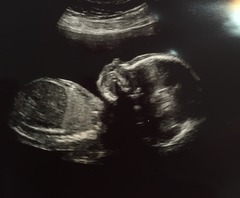

That's me back from our scan, went really well though baby was wriggling around loads. Managed to see and measure everything and all looking good, though seem to span percentiles, head was 54th, abdomen was 24th and leg was 36th. They didn't seem concerned though, so I'm not worried. Right at the end the baby stuck 2 fingers up which was very funny.

HAHAHA!!! Oh Lordy that's so funny lily! What an excellent pic for the album!!

Amazing picture! Congrats on a good scan.

Lovely pictures Lily Mine has a completely average head, a big belly and little legs! Sonographer said everything looked perfect so am not going to look anything up!

Congrats Lily

I think the 20 week pictures look so cute. I was very cynical before becoming pregnant and always thought 'its just a scan they all look the same, how can it be cute???' but I appear to have gone soft now!

Lily what great pictures! And a little insight into how cheeky I'm sure your little one will be!

Congrats Lily! Such a funny pic too for the album Grin

Love that picture Lily - hilarious!

Fab scan pics lily!! Love baby swearing at you - you're gonna have your hands full with her! Grin